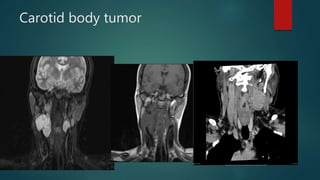

Carotid body tumor